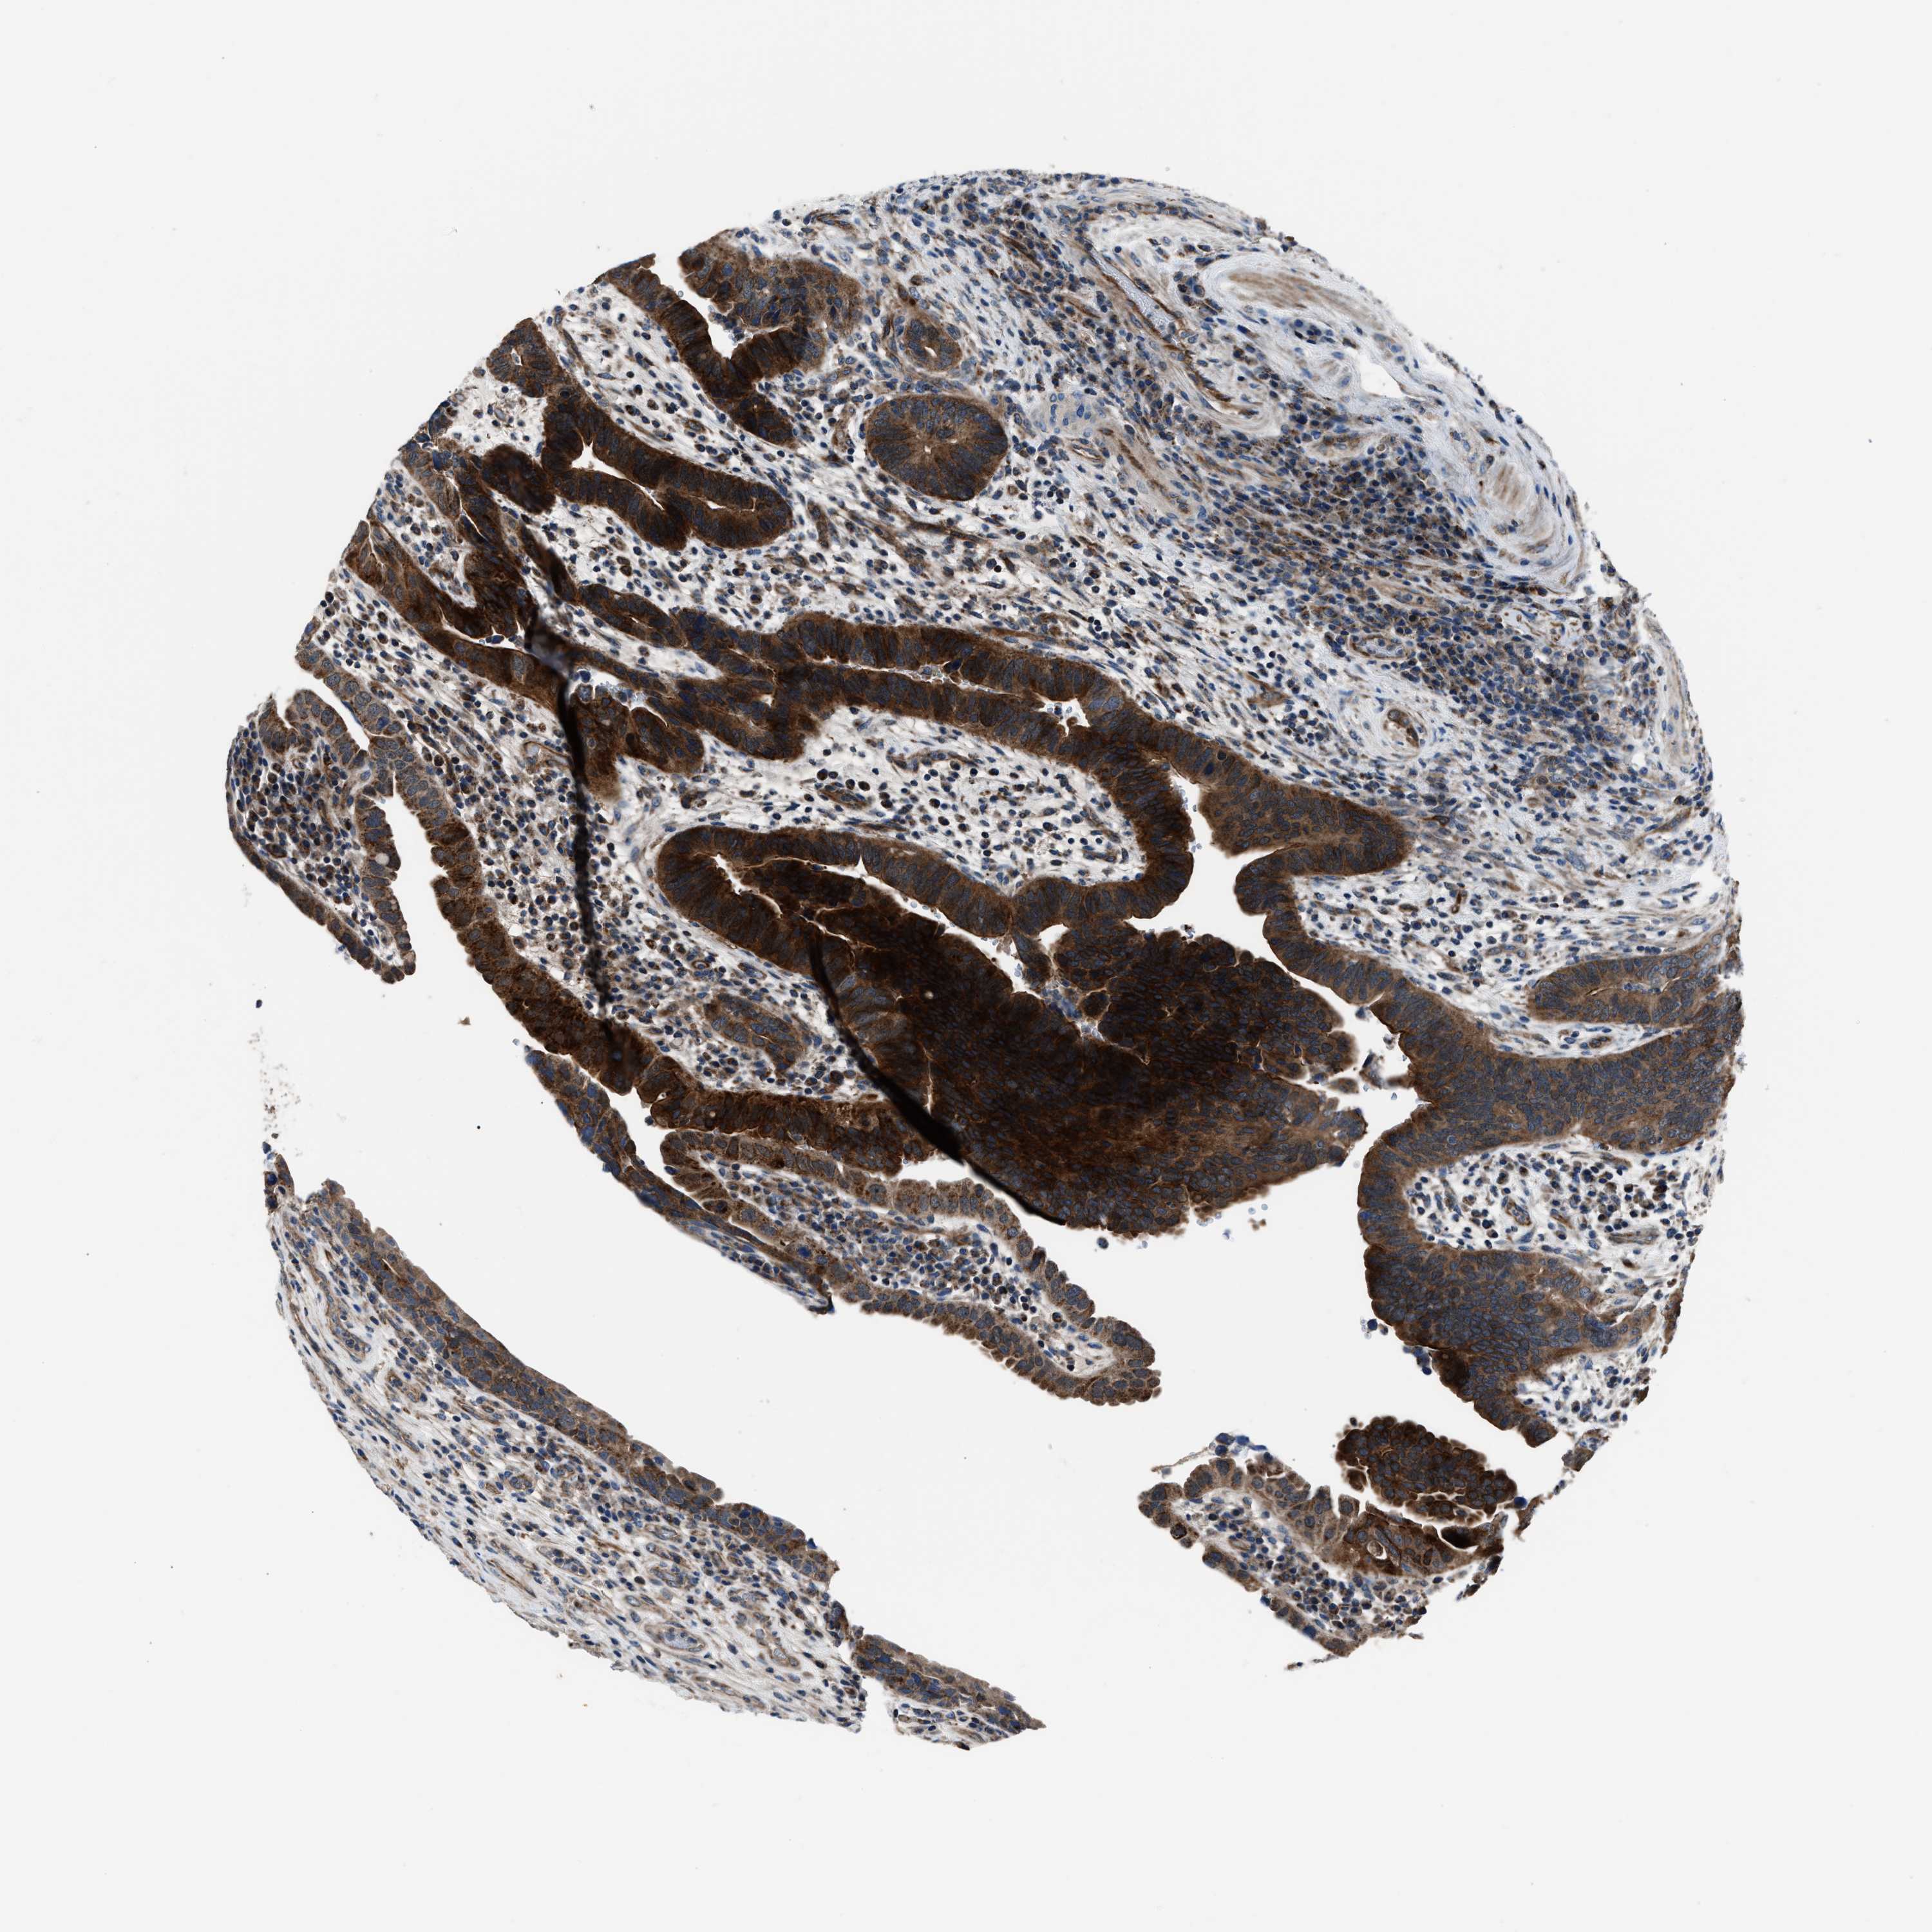

UROTHELIAL CANCER - Protein expressioni

A mouse-over function shows sample information and annotation data. Click on an image to view it in a full screen mode. Samples can be filtered based on level of antibody staining by selecting one or several of the following categories: high, medium, low and not detected. The assay and annotation is described here.

Antibody stainingi

Antibody staining in the annotated cell types in the current human tissue is reported as not detected, low, medium, or high, based on conventional immunohistochemistry profiling in selected tissues. This score is based on the combination of the staining intensity and fraction of stained cells.

Each image is clickable and will lead to virtual microscopy that enables deeper exploration of all samples and also displays staining intensity scores, fraction scores and subcellular localization as well as patient and tissue information for each sample.

Antibody HPA020735

Staining

High

Medium

Low

Not detected

Intensity

Strong

Moderate

Weak

Negative

Quantity

>75%

75%-25%

<25%

None

Location

Nuclear

Cytoplasmic/membranous

Cytoplasmic/membranous,nuclear

Urothelial carcinoma, Low grade

Urothelial carcinoma, High grade